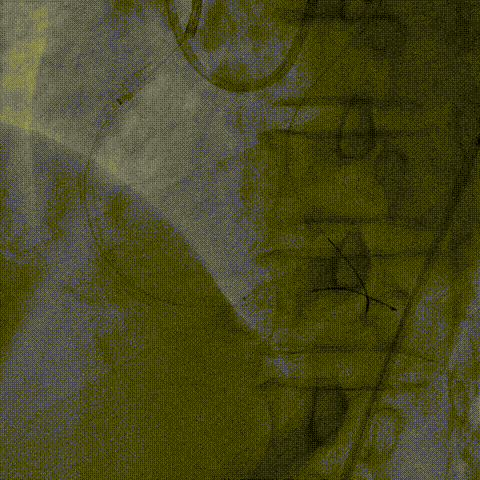

血管内超声:

导丝远端位于血管真腔,闭塞段部分内膜下走行,可见闭塞段钙化,符合术前评估结果。

支架植入:

根据血管内超声结果,在Telescope™支撑下序贯植入3.0mm、3.5mm、4.0mm支架3枚,4.0mm直径支架通过Telescope™延长管顺畅,无连接部剐蹭情况。

6F Telescope 支撑下序贯植入Ø3.0 3.5 4.0mm支架,通过性优异